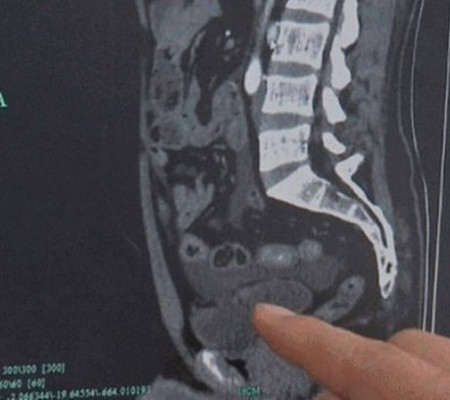

Depois de realizar uma tomografia computadorizada, os médicos ficaram chocados ao descobrir que a bexiga dele tinha se rompido em três lugares. Uma das lacerações se abriu em direção à cavidade abdominal e fez com que parte do intestino entrasse na bexiga. Hu foi imediatamente submetido a uma cirurgia. Os cirurgiões disseram ao jornal chinês que o paciente poderia ter morrido se as lacerações não tivessem sido reparadas a tempo.